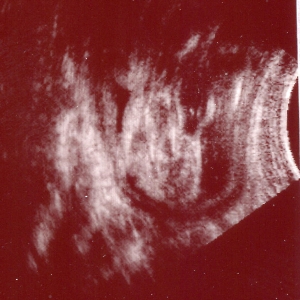

一応、女の子だという超音波写真です